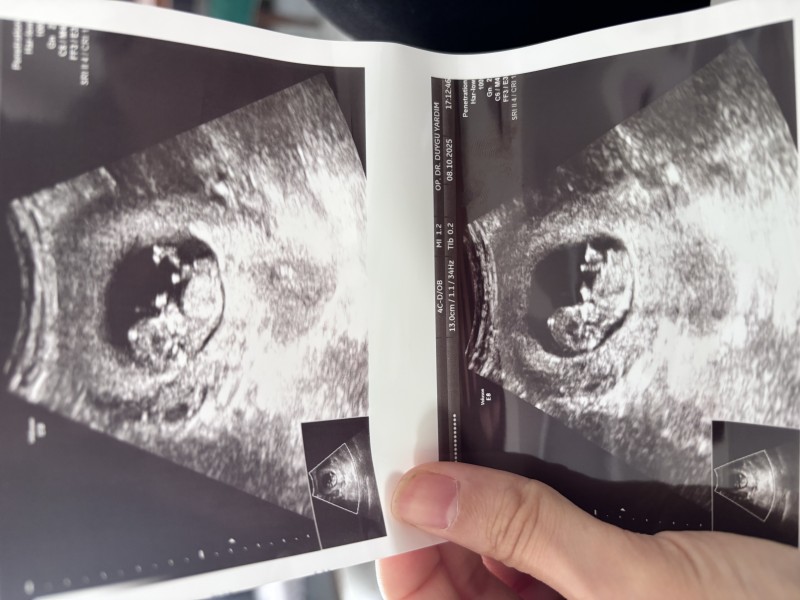

Kızlar cinsiyet tahmini nasıl neye göre yapılıyor hiç anlamıyorum ama bende bi sormak istedim bana da tahmin yapabilir misiniz 😊

Başı büyük, tepesi yassı duruyor. Erkek diyorum.

Keseye göre dersek benimki de böyleydi kız bebek oldu

Benim bebegime benziyor kiz

Kesin erkektir öğrendiğimde bana yaz

Kız bence canım ögrenince yaz mutlaka canım yine doğru yanlış mı bilicem:)

Ayy aynı haftada benimde aynı böyleydi ultrason fotorafım hatta cok kibar bence kız diyordum ama ogluşum oldu :))